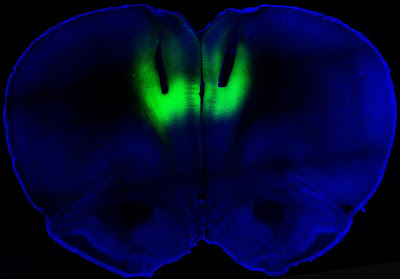

Wow, indeed. It didn’t take long for the science fiction technology of optogenetics to make itself felt in addiction studies. The idea of using targeted laser light to strengthen or weaken signals along neural pathways has proven surprisingly robust. The study by the NIH and the University of California at San Francisco, published in Nature, showed that lab rats engineered to carry light-activated neurons in the prefrontal cortex could be deterred from seeking cocaine. Conversely, laser light used in a way that reduced signaling in this part of the brain led previously sober rats to develop a taste for the drug. As Collins described the work:

All this light zapping took place in a brain region known as the prelimbic cortex. In their paper, Billy T. Chen and coworkers said that they “targeted deep-layer pyramidal prelimbic cortex neurons because they project to brain structures implicated in drug-seeking behavior, including the nucleus accumbens, dorsal striatum and amygdala.” These three subcortical regions are rich in dopamine receptors. In rats that had been challenged with foot shocks before being offered cocaine, “optogenetic prelimbic cortex stimulation significantly prevented compulsive cocaine seeking, whereas optogenetic prelimbic cortex inhibition significantly increased compulsive cocaine seeking.”

Photo credit: Billy Chen and Antonello Bonci